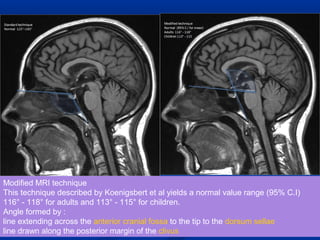

Modified MRI technique

This technique described by Koenigsbert et al yields a normal value range (95% C.I)

116° - 118° for adults and 113° - 115° for children.

Angle formed by :

line extending across the anterior cranial fossa to the tip to the dorsum sellae

line drawn along the posterior margin of the clivus